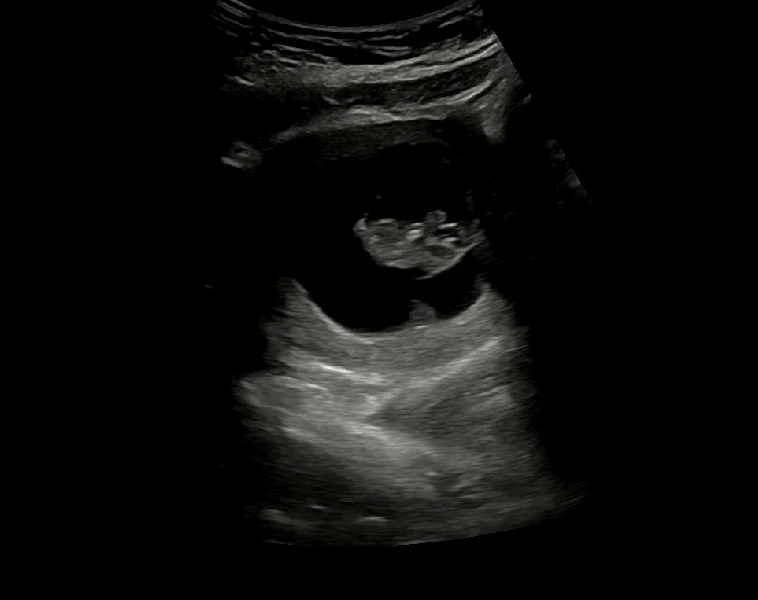

임신 9주차 초음파 (2023. 2. 11)

9주차에도 사이좋게 남편이랑 초음파를 보고 왔다! 초음파 속 사진이 뭐가 무엇인지 정확하게 잘은 모르지만 (ㅎㅎㅎ) 그저 신기해.